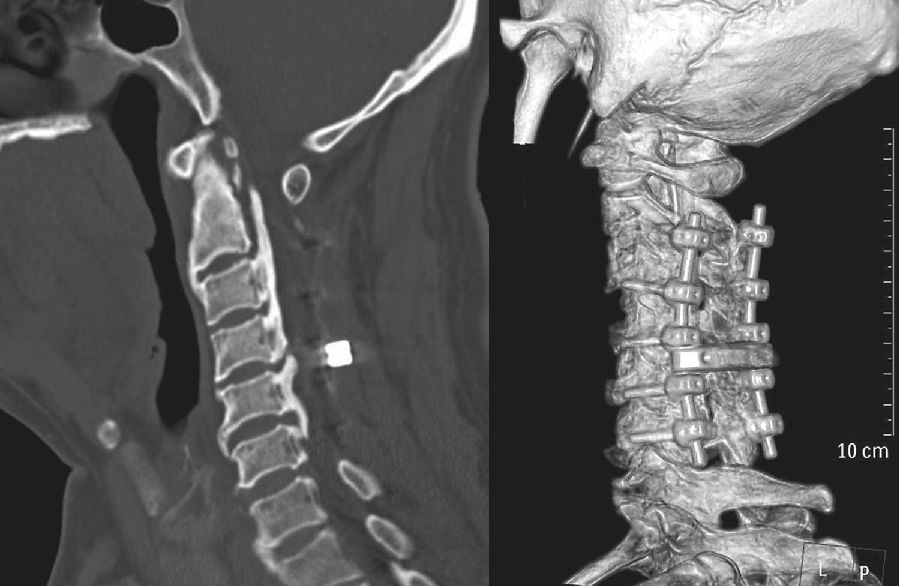

术后给予激素、补液及支持对症治疗,右手麻木较前好转,右侧肢体出现无力,左侧肢体出现麻木,疼痛感不明显,经康复治疗后,右手环指及小指仍感无力,余肢体麻木及无力较前好转,仍对生活及工作有影响。复查颈椎磁共振(MRI)示:C2-6椎板减压及内固定术后状态(图2),C4-6脊髓稍变细,以 C5-6节段显著,C2-6后纵韧带钙化(图2);CT三维重建钉棒系统位置良好(图3);术后3个月复查磁共振(MRI),髓内异常信号较前缩小,颈椎生理曲度变直(图4);术后11个月复查磁共振(MRI)示C4-5、C4-6椎间盘突出,脊髓受压明显,颈椎生理曲度进一步变直(图5)。

图3 术后1周CT;术后1周CT三维重建示钉棒系统位置良好